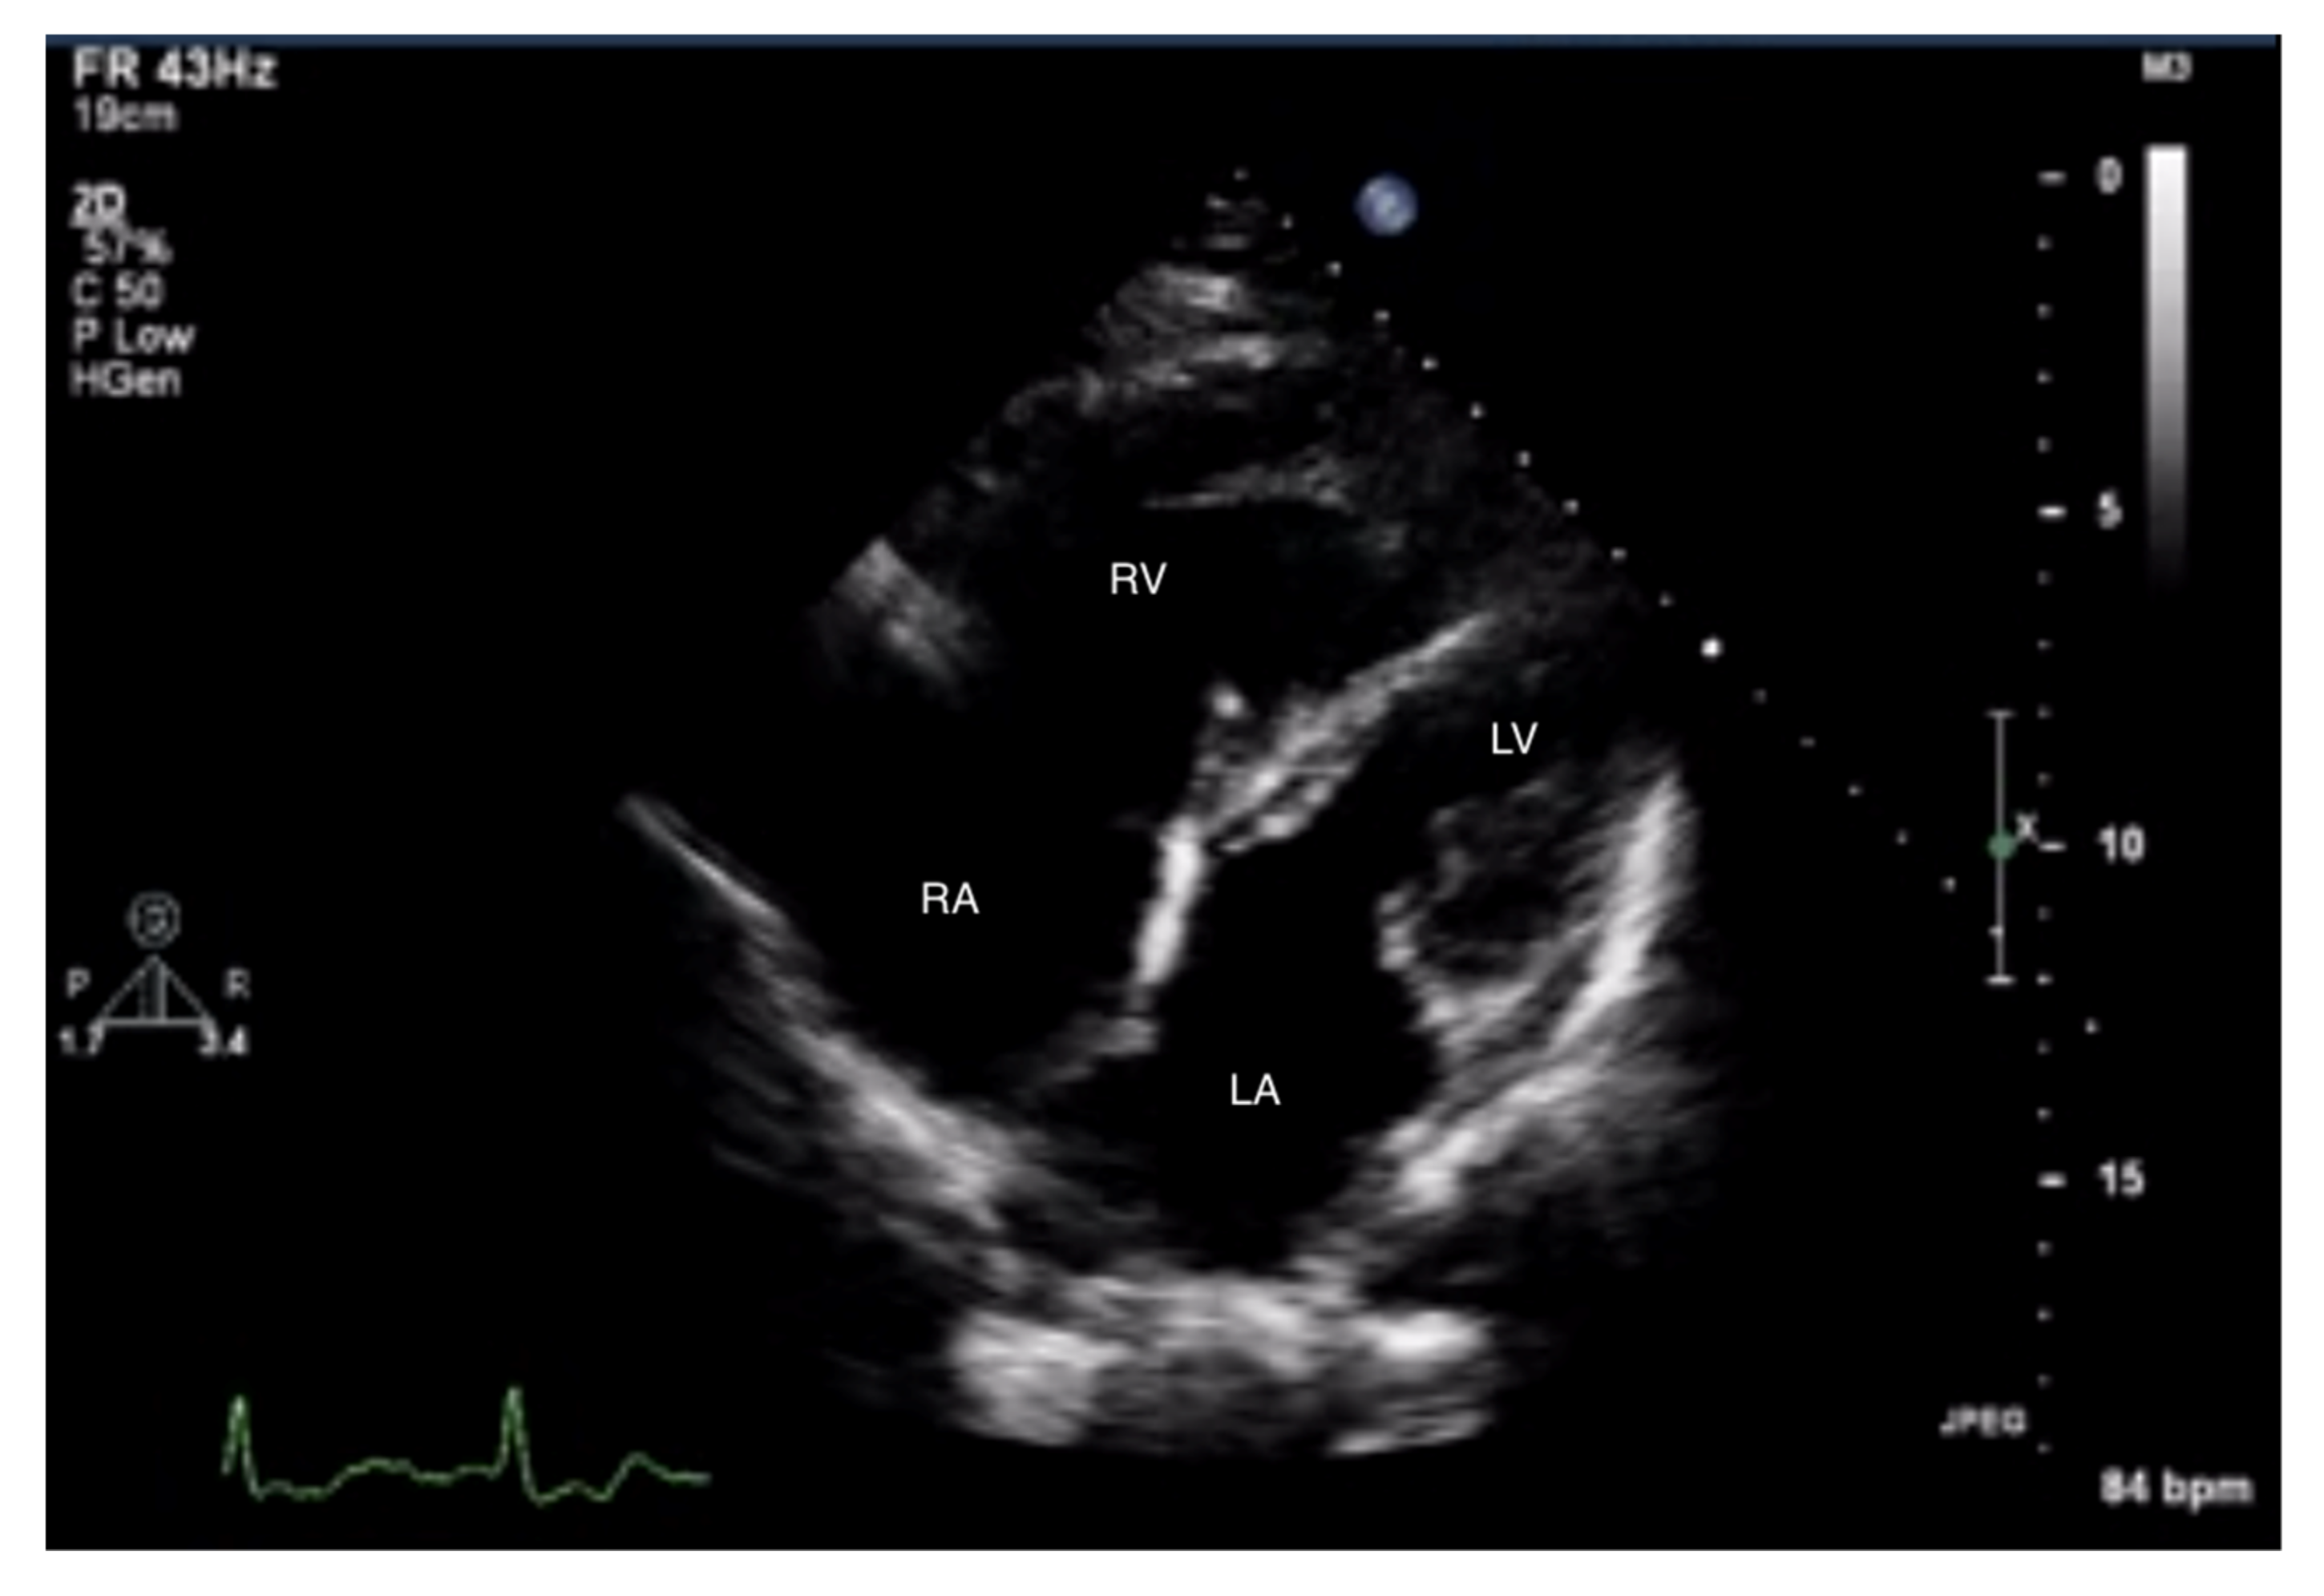

When pulmonary circulation pressure increases in the course of PAH, the right ventricle (RV) is subjected to overload. Initially, it adapts to an increased vascular load by increasing muscle contraction force by up to 5-fold, thus maintaining normal stroke volume values. To maintain the increased contractility, the right ventricular muscle mass increases [10], and wall hypertrophy and RV cavity dilatation occur [11]. Thus, in the course of PAH, there are changes in the size ratio between the two ventricles. In advanced stages, the right ventricle is larger than the left (Figure 1 and Figure 2). Statistically, in patients with PAH, the RV is more dilated and functions worse than in other diseases characterized by pulmonary hypertension [12].

Measurements of both ventricles are recommended in the four-chamber (4CH) view, and the correct projection during measurements should be maintained (Figure 3 and Figure 4). In assessing the linear dimension of the right ventricle, the goal should be to obtain the maximum dimension of the right ventricle while preserving the visibility of the apex and the plane of section passing through the center of the LV. RV measurement in a five-chamber view with a visible left ventricular outflow tract is erroneous [13]. Under these measurement conditions, the normal RV size should not exceed 2/3 of the LV dimension [14].

Figure 3.

Enlarged right ventricle and right atrium. An abnormal size ratio between the right and left heart. 2D-TTE, 4CH view. 2D-TTE: two-dimensional transthoracic echocardiography; 4CH: four-chamber.

Figure 4.

Enlarged right ventricle and right atrium. Tricuspid regurgitation. 2D-TTE, RV-focused apical 4CH view.